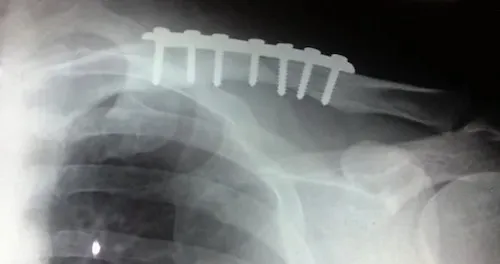

1. Gãy xương đòn (xương quai xanh) bao lâu quan hệ được?

Xương đòn là vị trí rất dễ tổn thương do ngã chống vai. Đây là vùng ảnh hưởng trực tiếp đến khả năng vận động của cánh tay và vai, vốn tham gia nhiều vào các tư thế quan hệ truyền thống.

Vậy gãy xương đòn bao lâu quan hệ được? Trong 2-3 tuần đầu, khi phải đeo đai số 8, vai cần được cố định. Việc quan hệ lúc này khá khó khăn và dễ gây đau.

Bạn nên chờ đợi ít nhất sau 3-4 tuần khi can xương bắt đầu hình thành.

Nhiều người thắc mắc gãy xương đòn có quan hệ được không sớm hơn mốc này? Thực tế là có thể, nếu bạn chọn tư thế nằm ngửa và bất động hoàn toàn vùng vai, nhưng sự thỏa mãn có thể không cao.

Với câu hỏi gãy xương đòn bao lâu mới quan hệ được thoải mái như bình thường, các bác sĩ thường khuyên nên đợi khoảng 6-8 tuần.

Một lưu ý nhỏ khác là gãy xương đòn có nên quan hệ được không còn phụ thuộc vào việc bạn có phẫu thuật hay không; vết mổ cần được lành lặn để tránh nhiễm trùng do mồ hôi hoặc cọ xát.

Tóm lại, gãy xương đòn bao lâu thì quan hệ được sẽ phụ thuộc vào việc bạn cảm thấy hết đau khi cử động vai nhẹ nhàng.